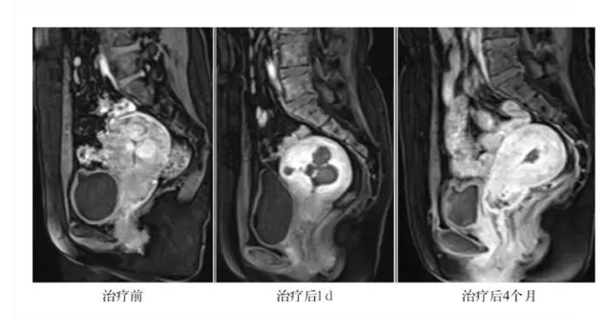

HIFU治疗是以超声波为能量源,通过利用超声波在人体的良好穿透性,将HIFU换能器产生的超声波聚焦于子宫肌瘤病灶内,通过超声波产生的热效应、机械效应、空化效应,在磁共振(MRI)或影像超声的监控下,准确消融目标肌瘤。由于治疗时仅在焦点处产生瞬间高热量,因此仅毁损靶区子宫肌瘤组织,而对超声能量经过的组织不造成损伤。HIFU治疗后,坏死的肌瘤逐渐被吸收、肌瘤缩小,子宫结构恢复正常(图1)。由于MRI及监控超声能准确发现2厘米以下小肌瘤,这为多发性子宫肌瘤患者提供了一个更简洁和更易接受的治疗选择,即可在不损伤机体和子宫正常肌层的前提下,同时实现对监控影像所见而手术难于发现的多个子宫小肌瘤的有效治疗。

1. 多发性子宫肌瘤HIFU治疗后的影像学变化。A 治疗前增强磁共振显示多个子宫肌瘤靠近宫腔,强化明显;

B. 治疗后1天增强磁共振显示多个肌瘤完全消融,周边结构正常;

C. 治疗后4月增强磁共振显示治疗的多个肌瘤被吸收,子宫形态恢复正常。